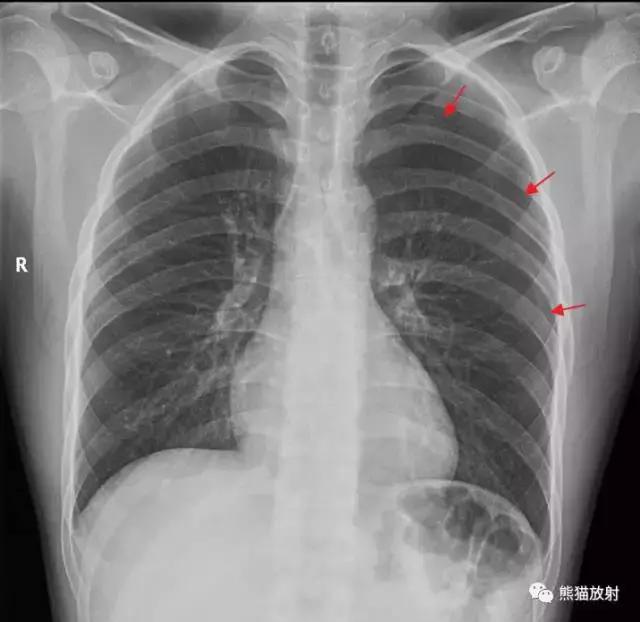

气胸影像图片,气胸胸片典型图片

气胸胸片典型图片